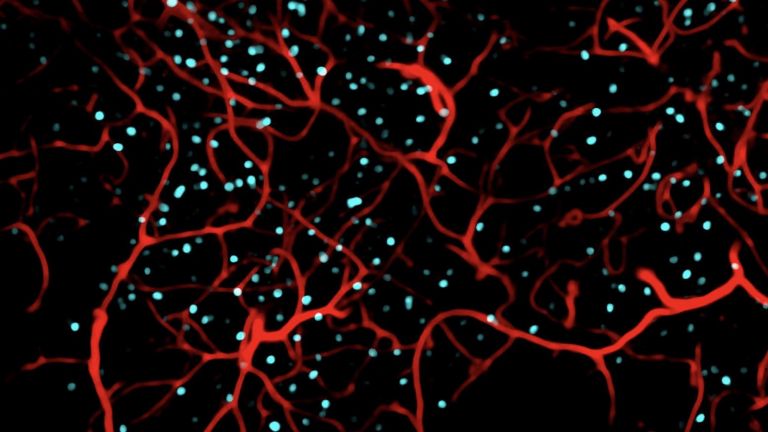

Offenbar hatte Karl Lashley bei seinen Studien am falschen Ort gesucht. In seinen Rattenexperimenten hatte er stets Teile der Hirnrinde, also der äußersten Schicht des Gehirns entfernt. Dieses Hirnareal ist in der Entwicklungsgeschichte des Gehirns das jüngste, alle anderen hielt Lashley für zu primitiv. H.M. fehlte es aber nicht an Hirnrinde, Scoville hatte einen Teil des Mandelkerns, der Amygdala, entfernt und fast den gesamten Hippocampus. Diese Region an der Innenseite der Schläfenlappen war offenbar entscheidend für das Formen neuer Erinnerungen.

Das zeigte sich auch in Tierversuchen. „Nach den Erfahrungen mit H.M. sind tausende Untersuchungen an Ratten und anderen Tieren gemacht worden“, sagt Markowitsch. Sie alle zeigten dasselbe: Wird der Hippocampus beschädigt, beeinträchtigt das die Fähigkeit, neue Erinnerungen abzuspeichern. Buschhäher finden das Essen, das sie versteckt haben, nicht wieder und Ratten finden sich in Labyrinthen nicht mehr zurecht.

Eine weitere Merkwürdigkeit im Fall H.M: Ihm fehlte zwar das Langzeitgedächtnis, aber für ein paar Sekunden konnte er sich alles merken. Viele Versuche haben gezeigt, dass sein Kurzzeitgedächtnis in etwa so gut funktionierte wie das eines gesunden Menschen. Telefonnummern oder Wortlisten etwa konnte H.M. sich kurze Zeit merken, wurde er aber nach ein paar Minuten oder Stunden noch einmal gefragt, hatte er sie vergessen. „H.M. war der Paradefall, der gezeigt hat, dass der Hippocampus zentral ist für die Übertragung vom Kurzzeit– ins Langzeitgedächtnis“, sagt Markowitsch. Was auf lange Zeit abrufbar bleiben soll, das muss offenbar durch das Nadelöhr des Hippocampus. So haben Forscher mit bildgebenden Verfahren gezeigt, dass sich Menschen aus einer Liste von Wörtern an die am besten erinnern, bei deren Lernen der Hippocampus am stärksten aktiv war.